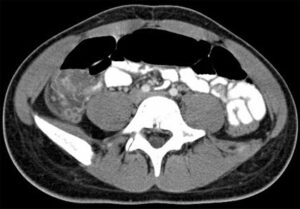

The two imaging modalities capable of quantifying adipose tissue from different compartments are MRI and CT. Each has its advantages and disadvantages. MRI can be acquired at a higher resolution than CT, allowing for the identification of smaller pockets of adipose tissue that would not be visible otherwise. The lack of radiation exposure from MRI allows for full body scans and thus more accurate quantification of adipose tissue. MRI signal intensity can vary with heterogeneities in the magnetic field, and slower scanning can produce artifacts from peristaltic movement in the gastrointestinal tract.

CT has a shorter acquisition time and thus produces clearer images without artifacts from peristaltic movement as in MRI. The attenuation values (in Hounsfield units) generated by CT are consistent between images, facilitating the accurate and straightforward identification of adipose tissue. However, CT carries the risk of increased radiation exposure. This can be managed by acquiring only a few sections instead of a whole body scan.

In the abdominal region, subcutaneous adipose tissue can be separated into superficial (SSAT) and deep (DSAT) compartments divided by Scarpa’s fascia, which is visible in MRI and CT images. There have been shown to be metabolic differences between superficial and deep subcutaneous adipose tissue. In particular, SSAT exhibits higher levels of expression of metabolic regulatory genes, while DSAT exhibits higher levels of expression of inflammatory genes. It has also been found that a higher volume of DSAT is correlated with insulin resistance and that adipocytes in DSAT exhibit more lipolytic activity than those in SSAT, so that a higher volume of DSAT correlates to a higher concentration of free fatty acids.

Visceral adipose tissue (VAT) also contains different types of adipose tissue that vary in their metabolic properties. VAT can be classified by which main body cavity it occurs in: intrathoracic adipose tissue (ITAT) in the thoracic cavity, intraabdominal adipose tissue (IAAT) in the abdominal cavity and intrapelvic adipose tissue (IPAT) in the pelvic cavity.